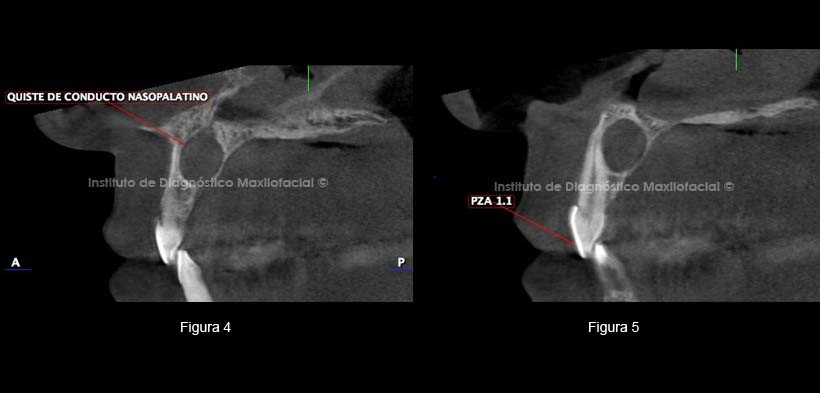

En un corte sagital a nivel de la línea media observamos la dilatación del conducto nasopalatino que produce adelgazamiento y erosión de la tabla ósea palatina (Figura 4) , en otro corte sagital vemos la relación con la pieza 1.1. (Figura 5).

En cortes coronales apreciamos la extensión de la lesión. Un corte vestibular donde se aprecia parte de piezas 1.1 y 2.1 (Figura 6) y el segundo corte en zona palatina de la lesión donde se observa más amplia (Figura 7).